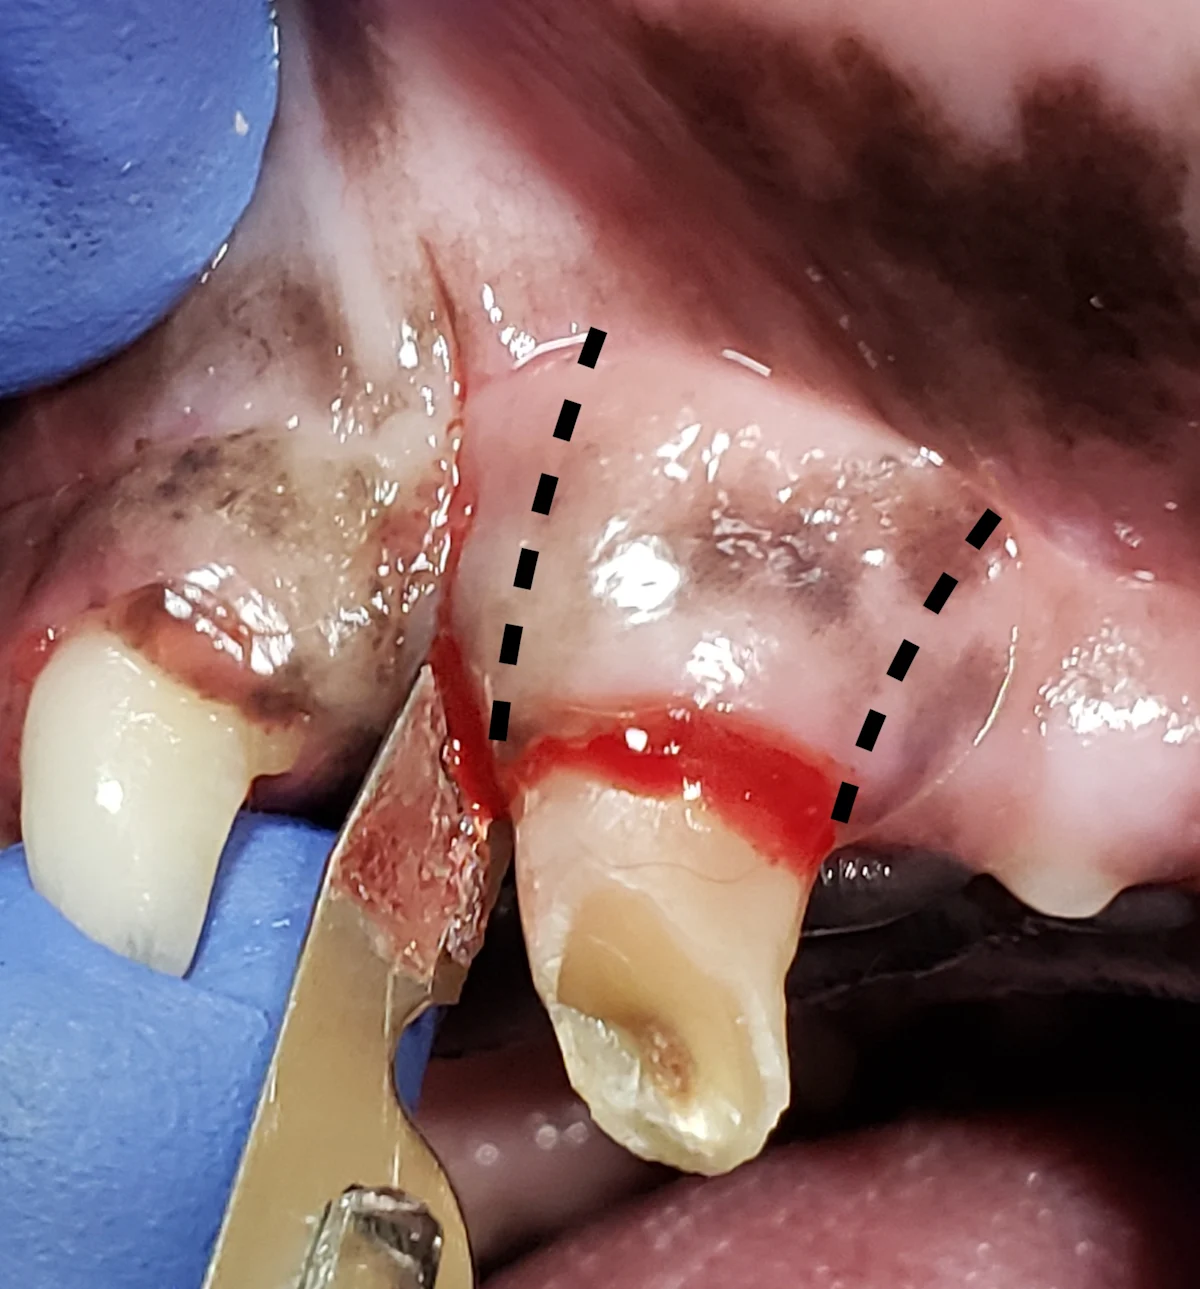

Step 2: Make Gingival Flap Releasing Incisions

Make releasing incisions for a full-thickness mucoperiosteal flap through the attached gingiva, past the mucogingival line, and at least a couple of millimeters into the alveolar mucosa to provide adequate exposure.

Flap Considerations

A rectangular, triangular, or envelope flap can be made.

Rectangular Flap

A rectangular flap is created by making a mesial incision and a distal incision angled away from the tooth, following the distally curving position of the root. Releasing incisions should extend at least to the level of the widest part of the root and should be slightly divergent from each other, keeping the alveolar mucosa at the base of the flap wider than the coronal aspect with the attached gingiva, to provide enough tissue for closure. A flap wider at the gingival margin is important if an oronasal fistula is present. Making releasing incisions 1 to 2 mm from the outline of the tooth edge (dotted lines) places the incisions over bone, enhancing access to the periodontal ligament space and supporting the suture line following closure. In the author’s experience, this flap design provides optimal accessibility for tooth elevation and does not result in disruption of blood supply during healing.